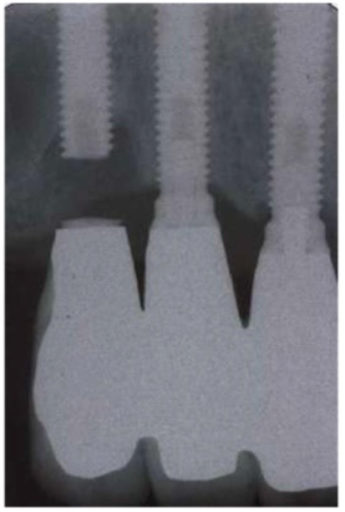

Vit bên dưới là vít của abutment Branemark bị gãy đã được lấy ra, so sánh với vít nguyên bên trên